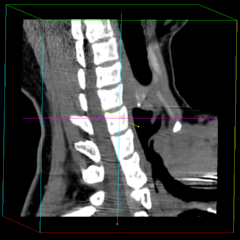

MPR表示について

CTやMRIなどの医療機器によって生成されたスライスシリーズ画像を表示する場合、MPR(多断面再構成)表示法は、非常に有効な読影方法であり、特に任意角度の斜断面画像の再構成(Oblique)表示法は、臨床診断に非常に有用かつ重要な読影手法となっています。

ImageClarityのMPR表示機能は、エンジンレベルで実現したもので、任意空間原点と任意3D方向の断面を表示することが可能になっており、補正表示をしながら実用レベルの高速表示を実現し、3D処理開発キットとしても非常に利用しやすいAPIを提供しています。 MPR以外に、任意サイズのMIP(最大値投影)表示法もサポートしています。

MPR/MIP表示